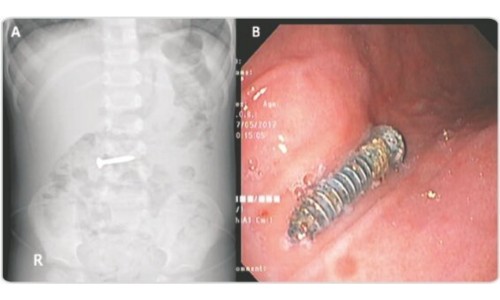

When a patient presents with suspected foreign body ingestion, our team conducts a thorough evaluation, including a detailed medical history, physical examination, and appropriate imaging studies such as X-rays or endoscopy. This comprehensive approach allows us to accurately identify the location, size, and nature of the foreign body, guiding our treatment strategy.

Endoscopy is often the preferred method for foreign body removal due to its minimally invasive nature and high success rates. At Adithya Gastro and Liver Care Clinic, we utilize advanced endoscopic techniques, such as flexible endoscopy and therapeutic accessories, to safely and effectively retrieve foreign bodies from the gastrointestinal tract.